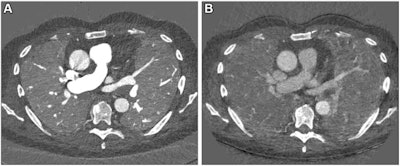

Chest CT is the gold standard for the evaluation of lung disease and for tracking disease progression, the researchers noted. But CT exams of lung function and blood flow require particular protocols that can't be combined. That's where PCCT comes in, offering high image quality, lower radiation dose compared to standard CT, better resolution, and spectral imaging options.

"The improvement in the contrast-to-noise ratio and spatial resolution of the pulmonary blood volume images was substantial," said corresponding author Dr. Hoen-oh Shin, also of Hannover Medical School, in a statement released by the RSNA. "In my opinion, the most important advantage is the significantly improved spectral resolution, which enables new applications such as functional imaging of the lungs with CT."

Scharm and colleagues developed a chest imaging protocol that produces structural and functional data from CT images with PCCT. The protocol requires advanced software but no additional equipment.

The protocol simultaneously evaluated patients' lung structure, ventilation, vasculature, and perfusion of the parenchyma, demonstrating advantages over standard CT, the team reported.